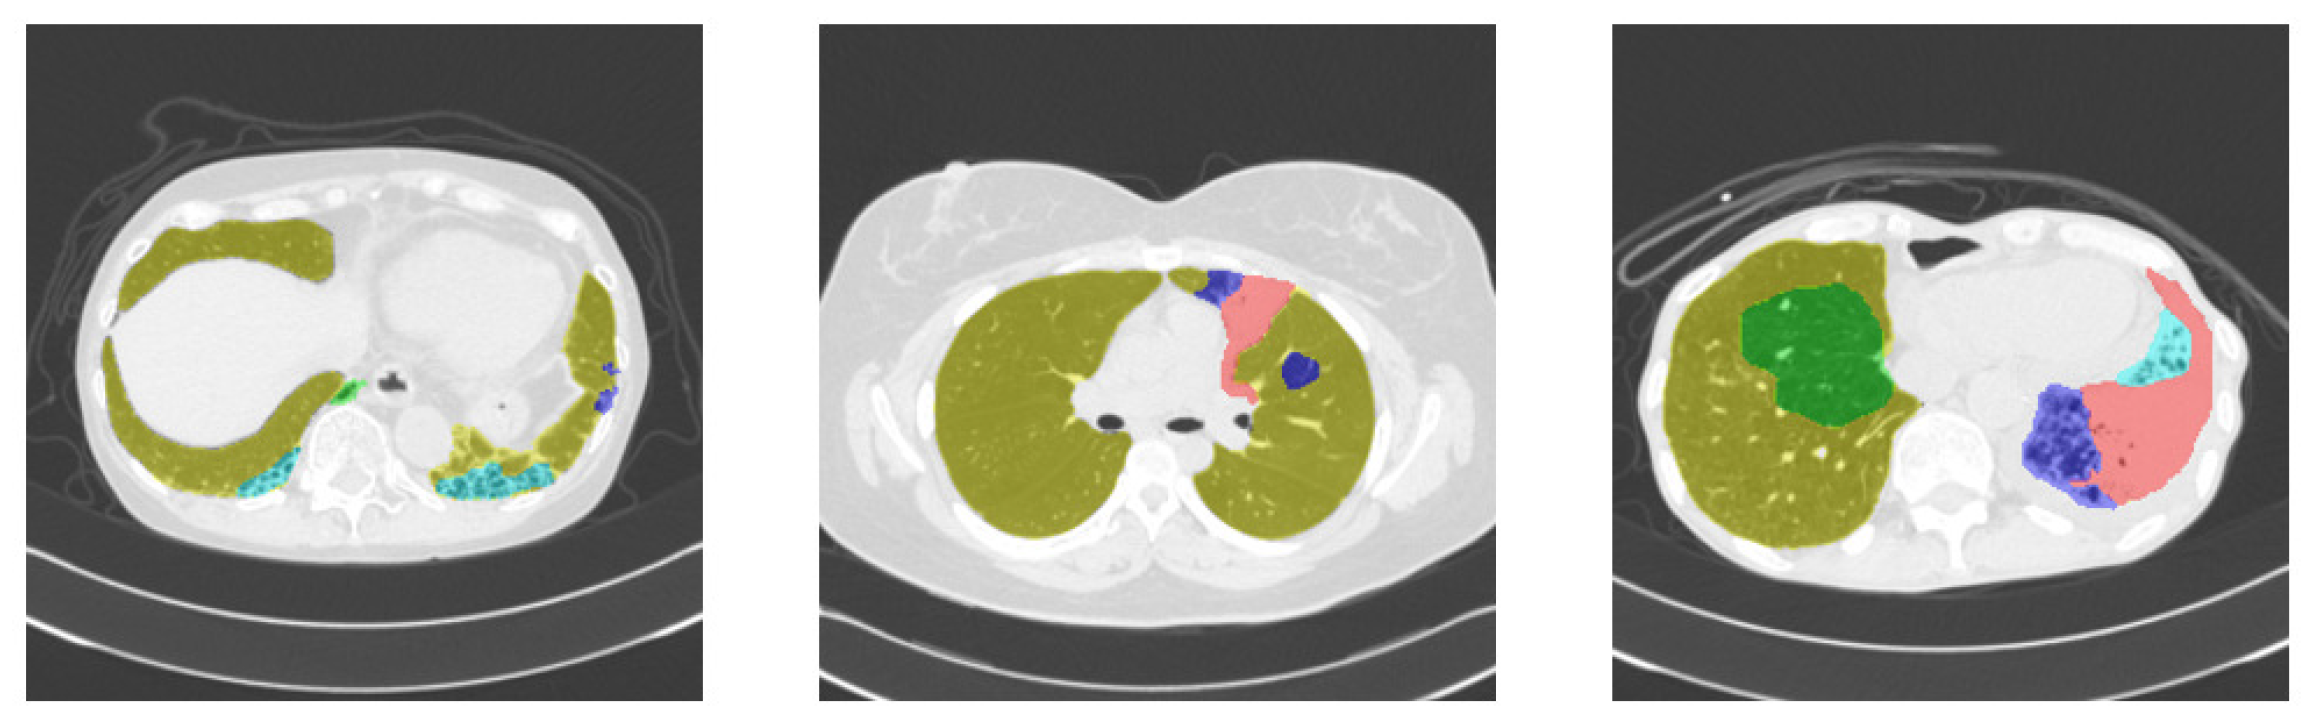

2.1. Dataset

- Suzuki, Y.; Kido, S.; Mabu, S.; Yanagawa, M.; Tomiyama, N.; Sato, Y. Segmentation of Diffuse Lung Abnormality Patterns on Computed Tomography Images using Partially Supervised Learning. Adv. Biomed. Eng. 2022, 11, 25–36. [Google Scholar] [CrossRef]